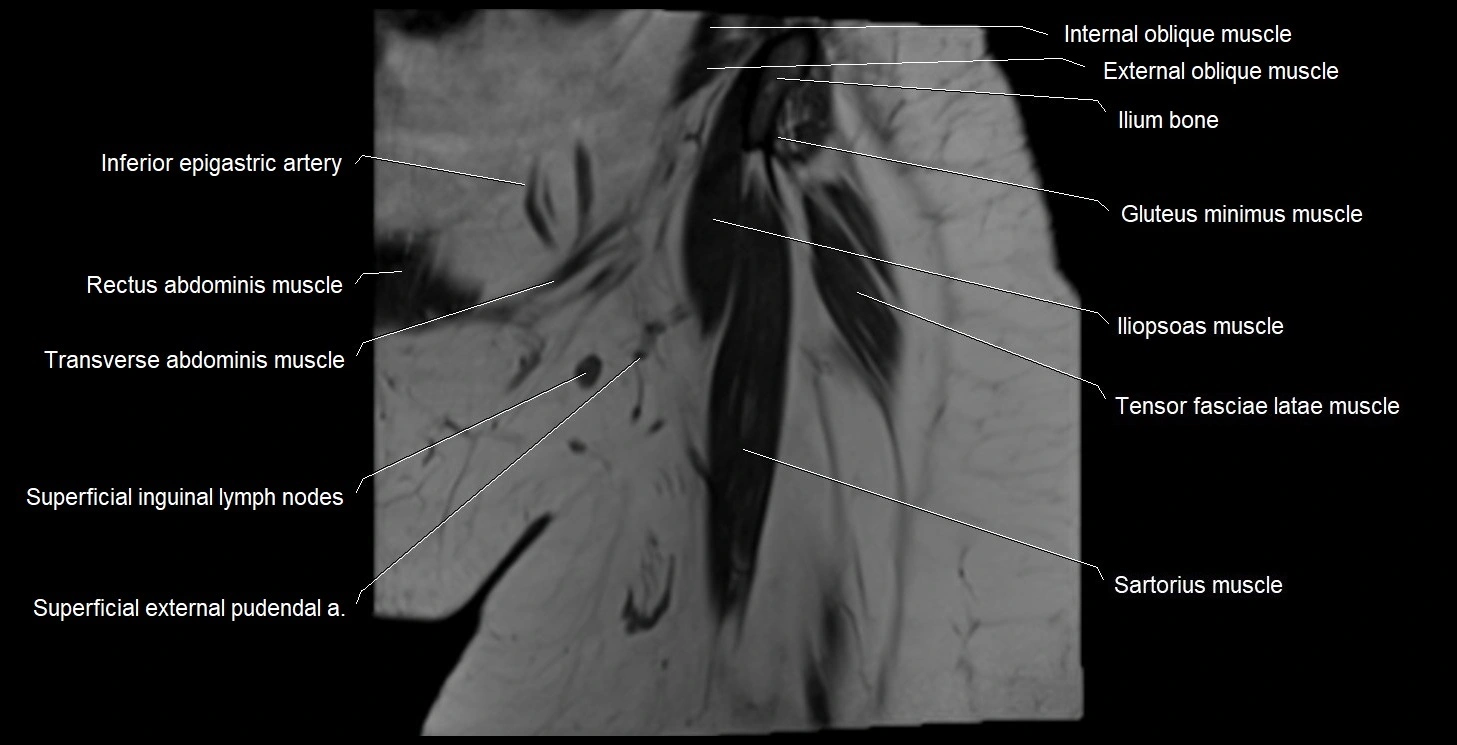

- Iliopsoas muscle

- Inferior epigastric artery

- Rectus femoris muscle

- Sartorius muscle

- Superficial inguinal lymph nodes

- Tensor fasciae latae muscle